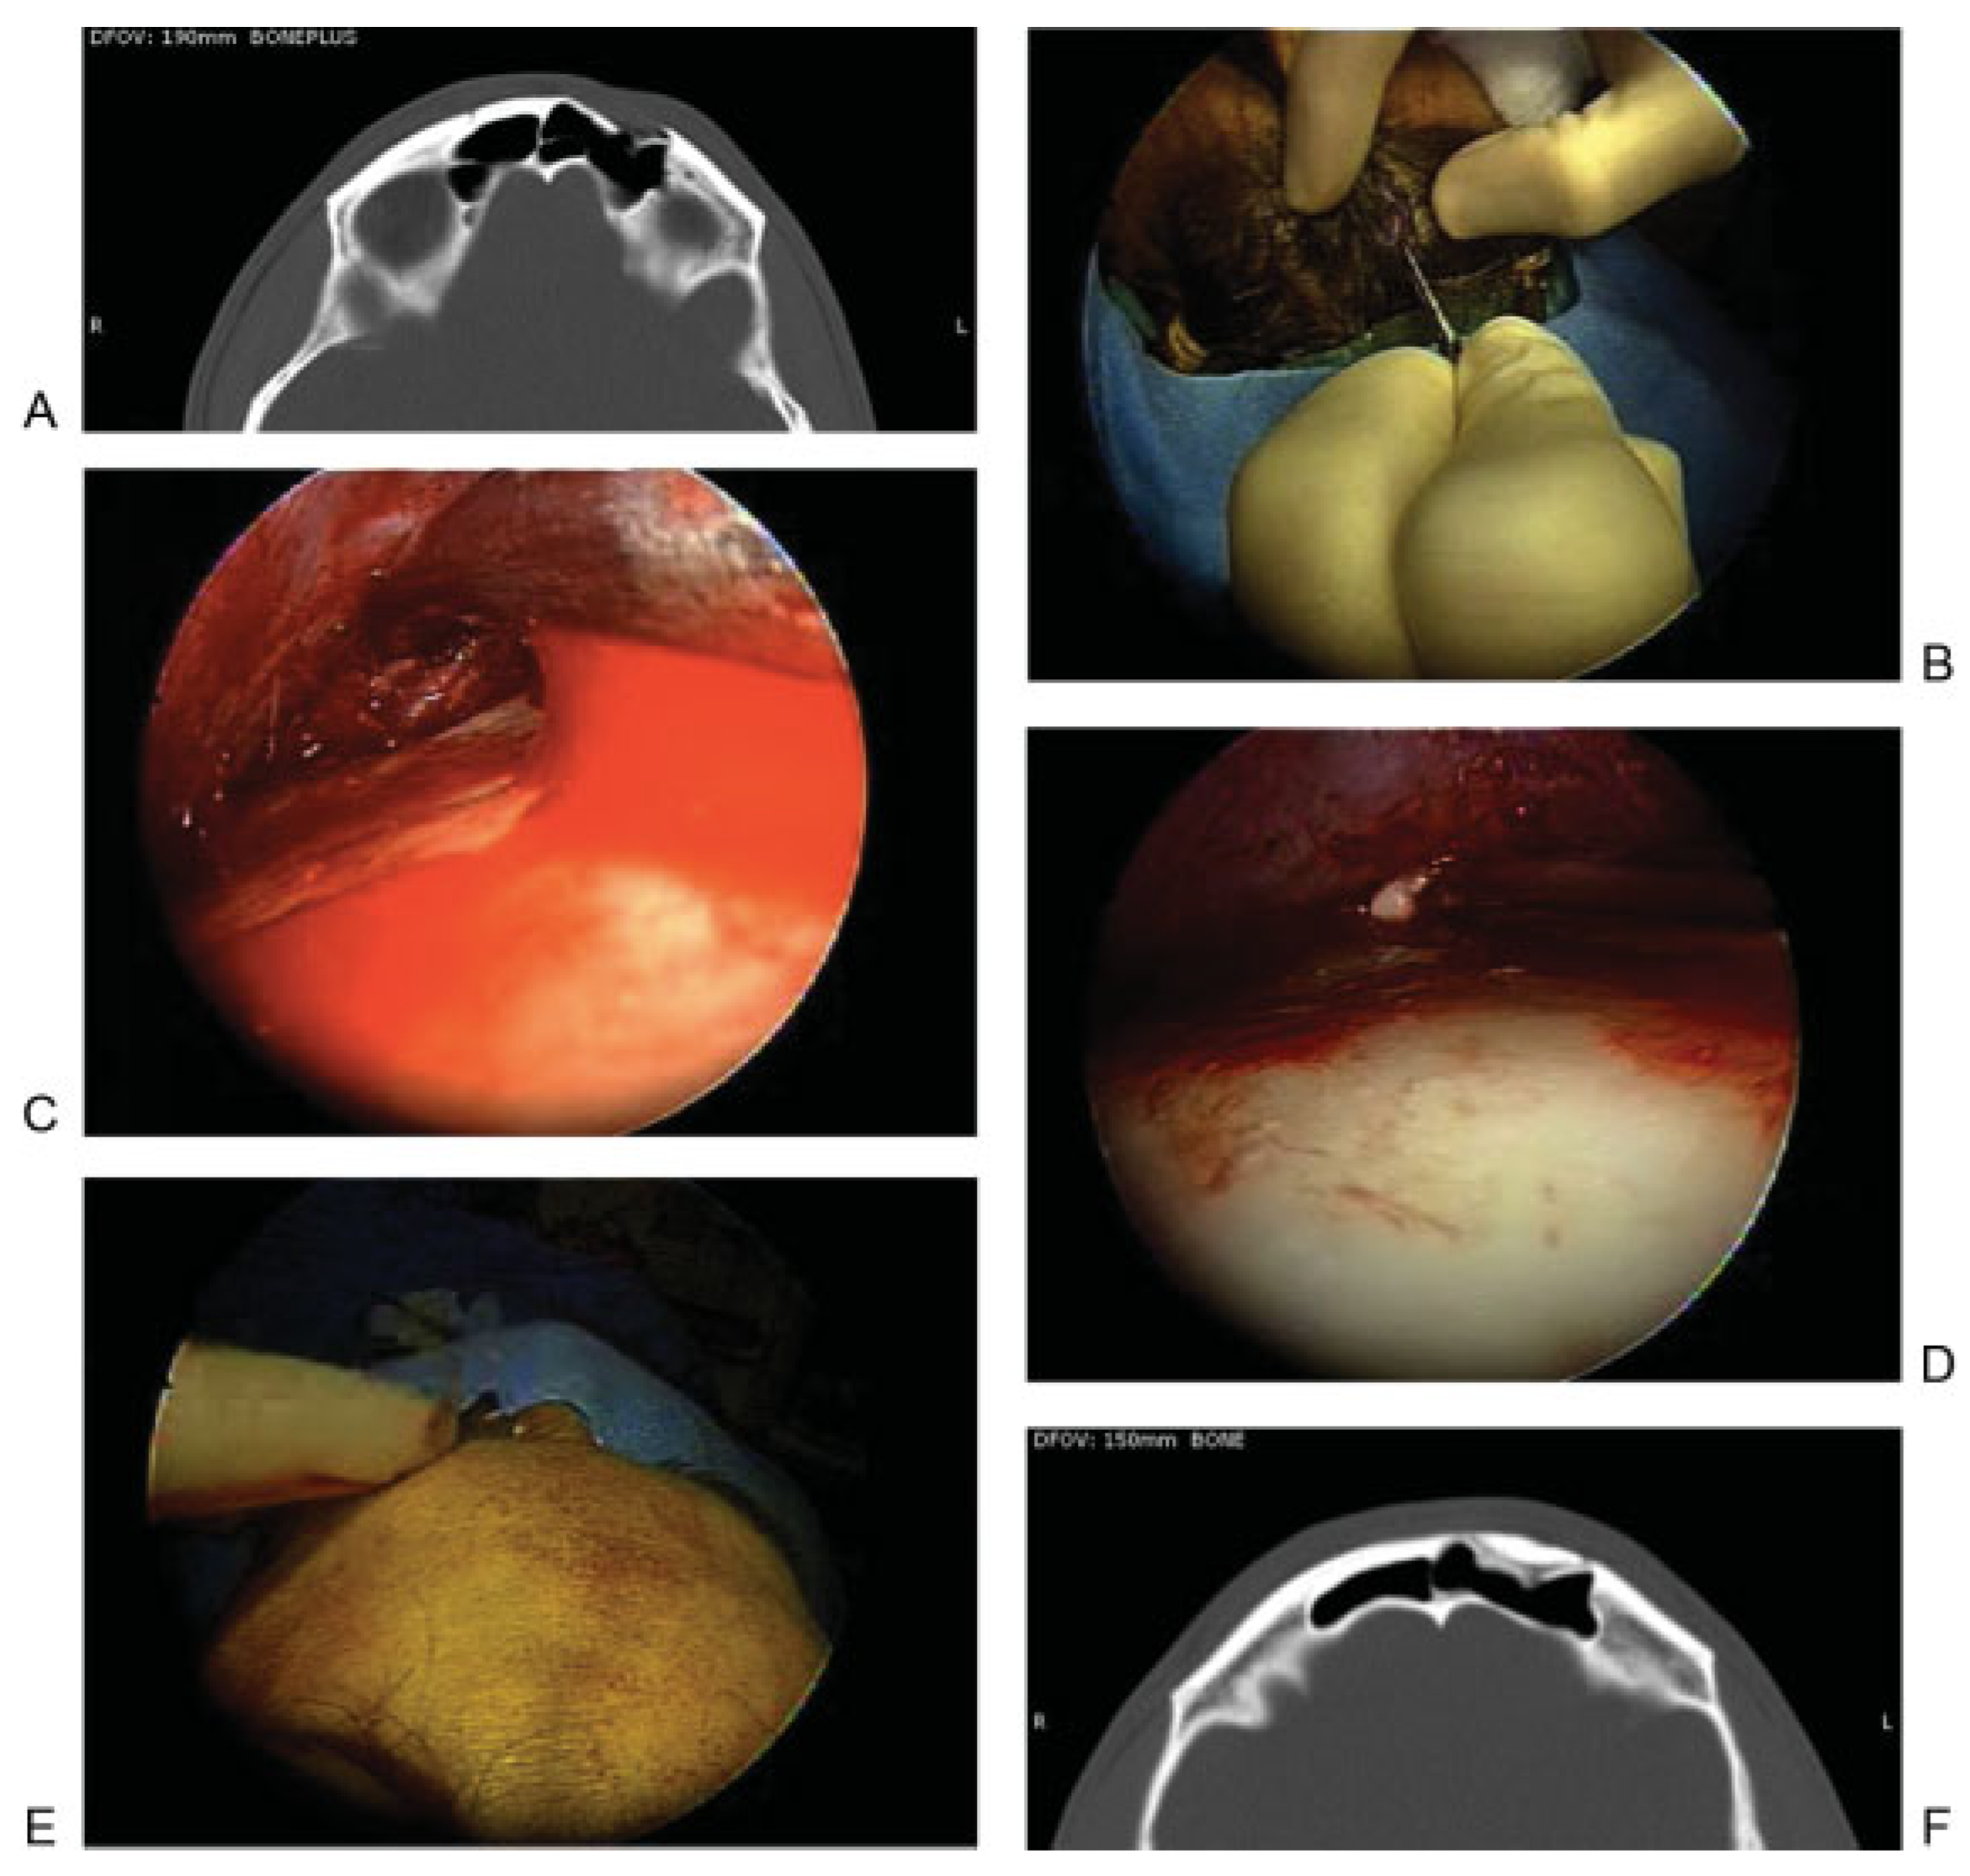

Figure 3.

(A)Axial computed tomographic image showing depression related to an anterior table fracture. (B–E) Intraoperative photographs showing repair of frontal depression related to an anterior table fracture. (B) After making an incision, (C) an endoscope is used to dissect in the subperiosteal plane and expose the depression. (D) Hydroxyapatite cement is then injected and gentle pressure is used to smooth the cement to restore the appropriate contour. (F) Axial postoperative image showing excellent restoration of the frontal contour after placement of bone cement.